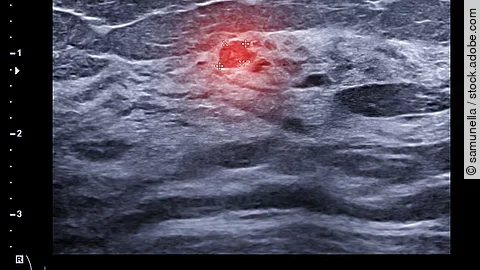

Expertenwissen wird über Standortgrenzen hinweg verfügbar sein: Das klinische Know-How sowie das MTR-Fachpersonal für die Dienstleistung kommt von Asklepios; Philips implementiert die Soft- und Hardware und führt den Service durch. Die herstellerneutrale multimodale Lösung befähigt MTRs (Medizinische Technolog*innen für Radiologie) Remote-Unterstützung per Audio- und Videoverbindung anzufordern. Erfahrene Fachkräfte schalten sich aus der Zentrale oder dem Homeoffice auf die Konsolen der Systeme, um das Personal vor Ort zu unterstützen. Alternativ führen sie Untersuchungen per Fernsteuerung durch, während sich die Fachkräfte vor Ort um die Patientenlagerung und Spulenpositionierung kümmern.